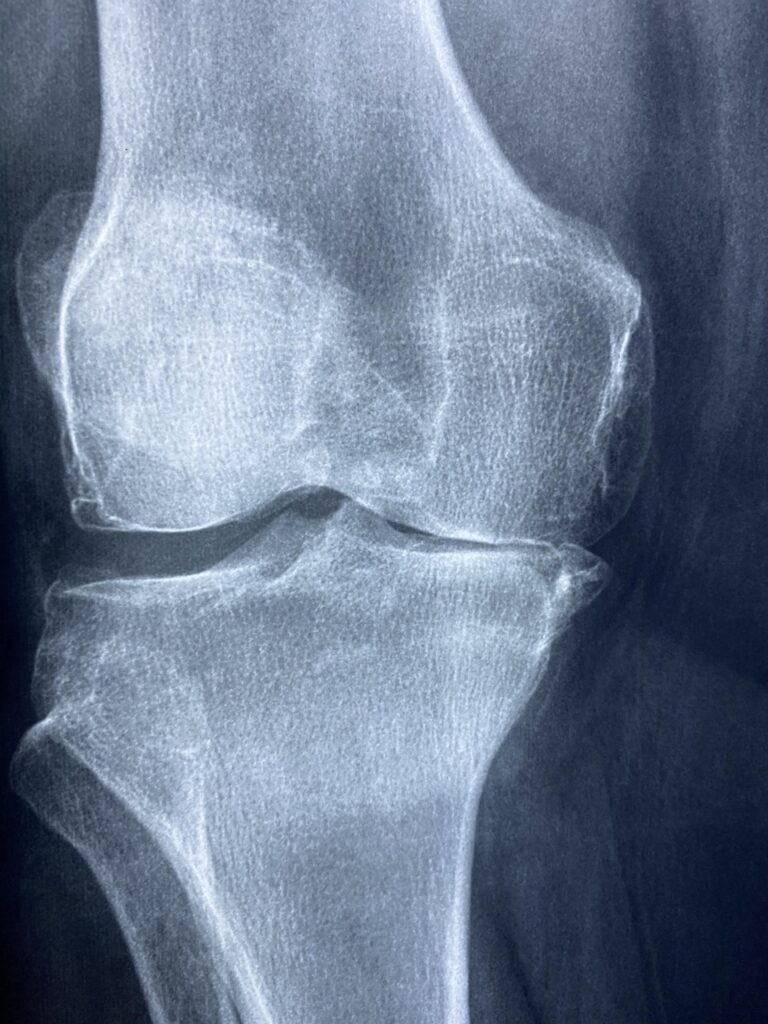

まず、膝の怪我にはいくつかの種類があります。代表的なものには、靭帯損傷、半月板損傷、膝蓋腱炎などがあります。これらは、急な動きや不適切なフォームから生じることが多いです。特に、野球のような激しいスポーツでは、膝にかかる負担が大きくなります。